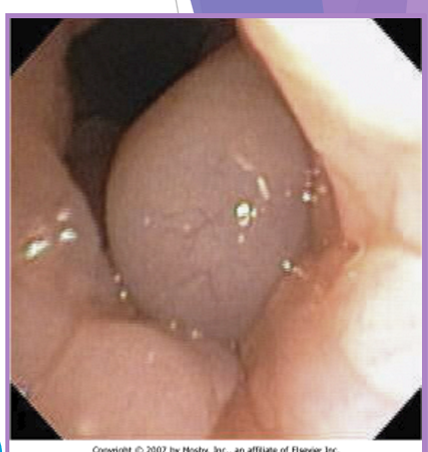

BOAS everted laryngeal saccules

prolapse of mucosa lining the laryngeal crypts

response to chronic high upper airway pressures

least common of the BAS complex

why a concern

further inhibit airflow, increases mucosal irritation

first stage of laryngeal collapse

surgical technique - cut them out but careful of vocal folds

extubate the patient temporarily

grasp and pull with forceps

resect saccule at its base with metzenbaum scissors

bleeding is controlled with direct pressure (from the ET tube)

happens due to chronic stress